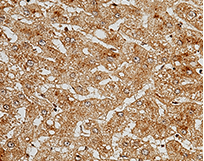

Anti-C5a, Rabbit mAb: (Cat#: 10604-R215)

Application: IHC-P

Immunochemical staining of human C5a in human cirrhosis. Image Credit: Sino Biological Inc.